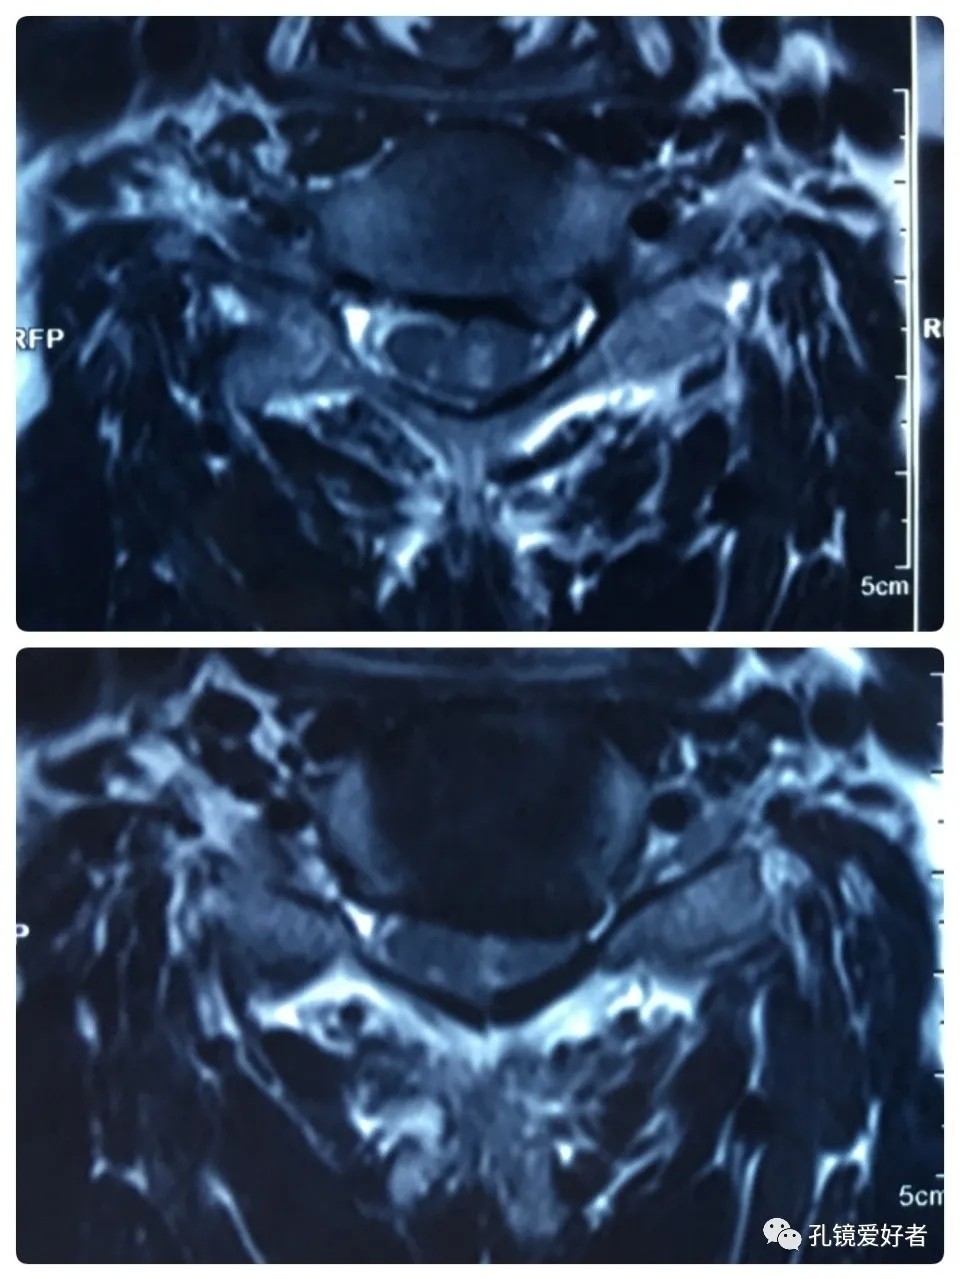

Plain MRI Scan

The patient's preoperative imaging data

Then let's look at MRI.

The MRI shows that the cervical stenosis is on C3-4, C5-6 and C6-7. Considering the patient's clinical symptoms, C5-6 and C6-7 are the main affected segments. So it’s advised that the patient undergo posterior cervical open-door laminoplasty. According to the patient, he had visited many hospitals before and received similar proposals of diagnosis and treatment- posterior cervical open-door laminoplasty. The reason he came to our hospital was that he wanted his surgery could be performed in a minimally invasive way. After considerable preoperative discussion with my colleagues and the patient, we decided to perform the minimally invasive endoscopic decompression for C5-6 and C6-7 double-segment stenosis through posterior approach (with the Delta system).